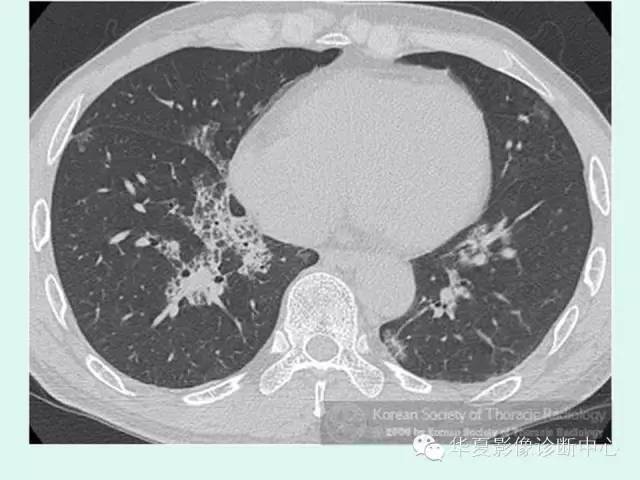

【病例】肺泡蛋白沉积症1例CT影像表现